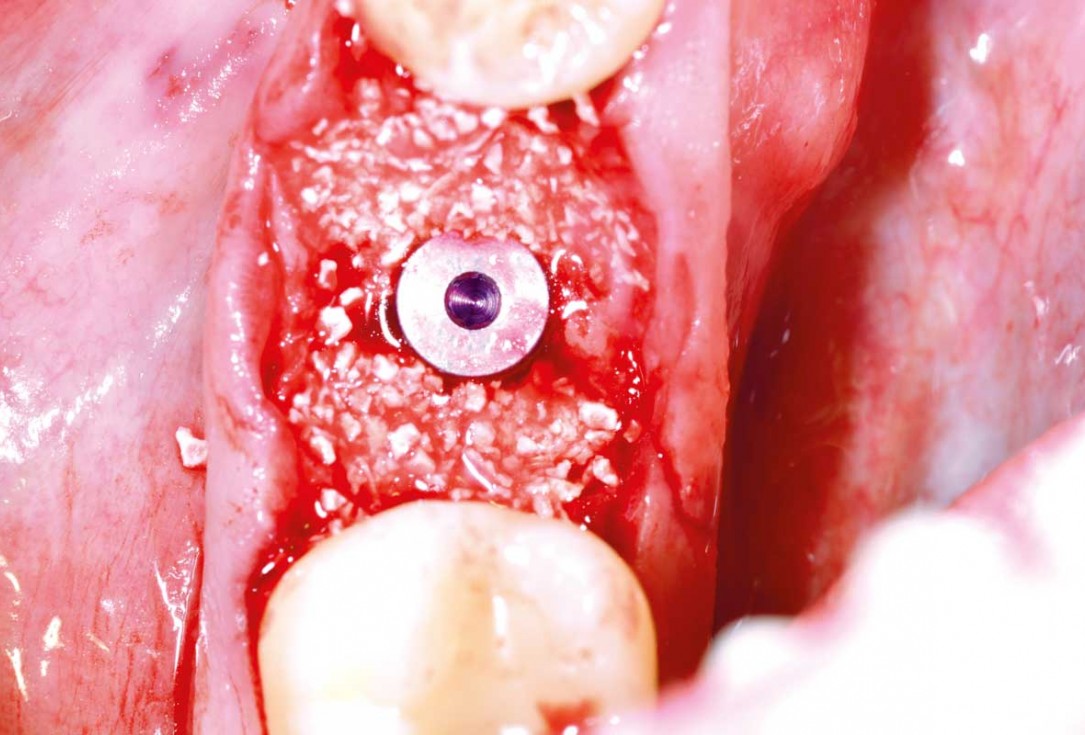

07/25 - Peri-implant missing bone augmented with cerabone® plusImmediate implant placement and peri-implant bone augmentation with cerabone® plus - Dr. R. Block Veras